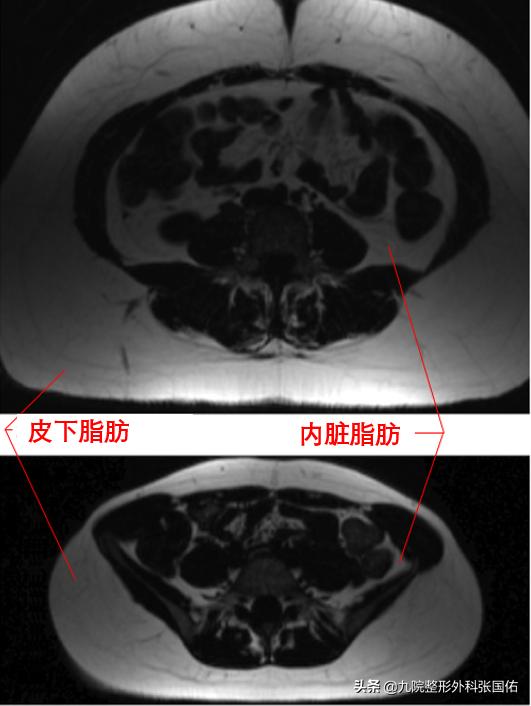

内脏脂肪与皮下脂肪之间的相似性

▶内脏脂肪和皮下脂肪是腹部脂肪的两种类型。

腹部皮下脂肪、内脏脂肪的CT检测

内脏脂肪和皮下脂肪有什么区别

▶定义: 内脏脂肪是指存储在腹腔和许多重要内部器官中的一种体脂,而皮下脂肪是指存储在皮肤下的另一种体脂;

▶发生: 内脏脂肪发生在填充于内部器官和躯干之间的腹膜腔内部,而皮下脂肪发生在皮肤的皮下组织中;

▶占比:内脏脂肪一般占体脂总量的6-20%,皮下脂肪一般占体脂总量的80%;

▶一般功能 :内脏脂肪起到保护垫的作用,而皮下脂肪则可以隔绝热和冷;

▶ 多余的脂肪:过多的内脏脂肪会导致中型肥胖或腹部脂肪,而过多的皮下脂肪不会导致经典的肥胖问题。

▶健康问题:内脏脂肪过多会导致2型糖尿病,胰岛素抵抗,炎症性疾病等,而皮下脂肪过多则可以起到保护作用。

▶活跃度:内脏脂肪通过引起健康问题而活跃,而皮下脂肪通过内分泌器官活跃。